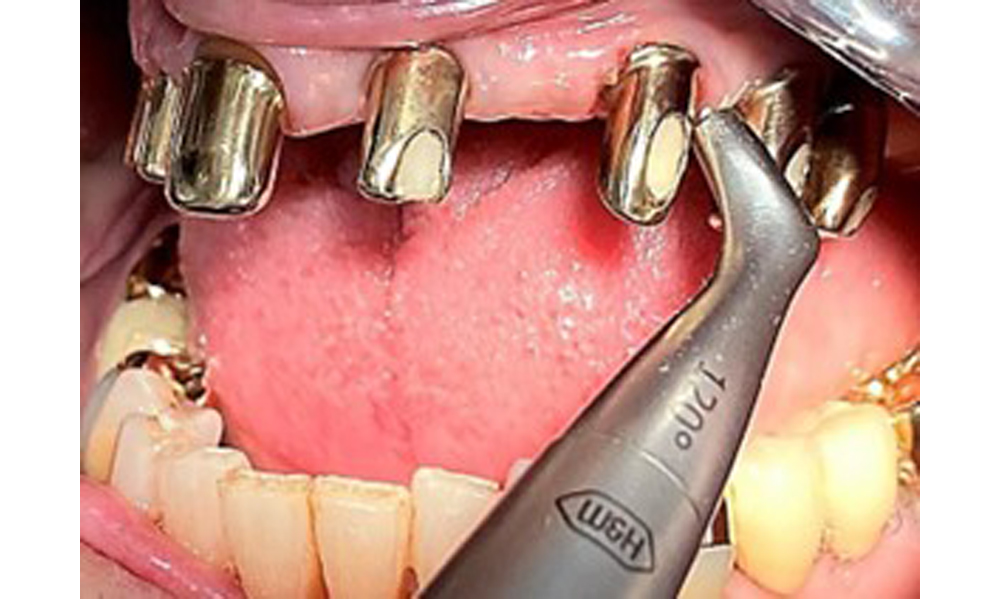

Illustration of a PEEK ultrasonic tip (Proxeo Ultra, W&H, shown here) for processing implant surfaces with mineralized plaque (no mineralized plaque was observed in the present case, this is a schematic illustration).

Fig. 11: Illustration of a PEEK ultrasonic tip (Proxeo Ultra, W&H, shown here) for processing implant surfaces with mineralized plaque (no mineralized plaque was observed in the present case, this is a schematic illustration).

Sonic/ultrasonic, or conventional manual instruments may be used to remove calculus and concretions present on the natural teeth (8). Titanium or plastic curettes (Fig. 10), or a plastic or PEEK attachment (Fig. 11) during ultrasonic treatment, should be used to remove mineralized plaque from implants to avoid damaging the implant surfaces.